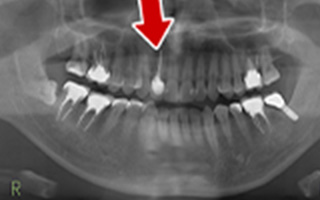

Before

After

| 60歳 男性 | 歯科大学病院 教授からの紹介 ご本人は産婦人科医 |

|---|---|

| 主訴 | 左下に歯が無くて食事がしずらい |

| 処置内容 | 2本インプラント埋入+再生処置 |

| 治療費用 | 下顎: 約80万円(税込) |

| 治療期間 | 下顎: 6ヶ月 |

| リスク | 術後の腫れ、痛み(ピークは3日後、1週間で軽減) |